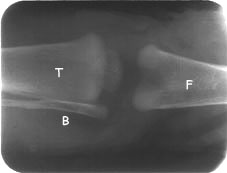

Tomada radiográfica no sentido ântero-posterior, mostrando  o fêmur (F), o tíbiotarso (T) e a fíbula (B). As tonalidades de branco a cinza-claro são denominadas "radiopacas" e as de cinza-escuro a pretas, "radiolúcidas"